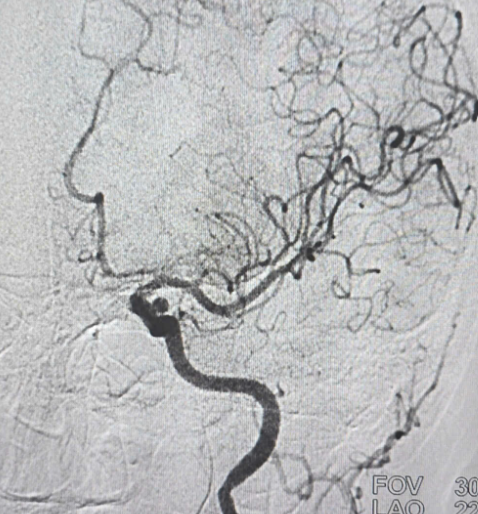

– Chụp cắt lớp vi tính mạch máu não.

– Chụp MRI/MRA.

– Chụp DSA mạch não.

– Can thiệp nội mạch (đặt coil, stent).

– Phẫu thuật kẹp cổ túi phình.